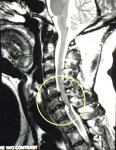

MRI image showing the upper disc issue. My C6-C7 vertebrae and discs are troublemakers. Rascals. Rebels. The insurgents of my spine. Both discs between the bones are nudging into my spinal cord, with C7 taking the lead. I’ve known about these discs since 2010 but the fact that they are still causing trouble after years of chiropractic care and two bouts of physical therapy is, well… troubling. Surgery is not recommended yet. Pain shots are forthcoming, I think.